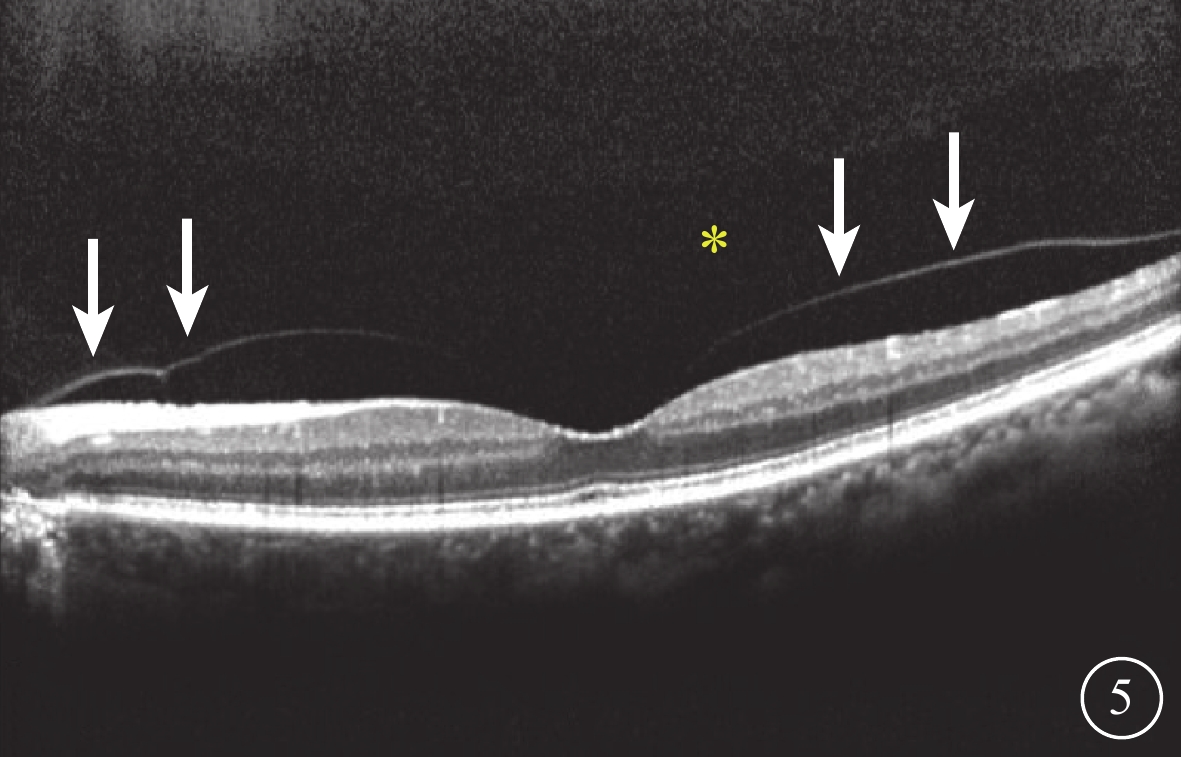

SD-OCT檢查,采用德國Heidelberg公司Spectralis OCT儀對黃斑和視盤進行橫向掃描,ART 60-100,波長870 nm,掃描寬度8.3 mm,掃描速度40 000次/s,掃描深度2.0 mm。檢查方法:(1)常規檢查,掃描焦點在視網膜。(2)后極部玻璃體掃描模式,掃描時視網膜圖像位于視窗偏下方,扭動掃描調焦旋鈕,使焦點稍往前移以加強后玻璃體成像,檢查黃斑區玻璃體的屈光補償約+2.00 D,視盤約+4.00 D。103只眼中,60只眼應用Heidelberg Eye Explorer軟件(version 1.9.10.0)手動測量圖像中結構完整的PPVP最大水平距離以及黃斑中心凹前垂直距離(圖1)。(3)全深度成像(FDI)掃描模式,在后極部玻璃體掃描模式基礎上,當圖像獲取到80%時立即啟動增強深部成像按鈕。103只眼中,采用FDI掃描模式檢查21只眼。

圖1

PPVP測量示意圖

圖1

PPVP測量示意圖

SD-OCT檢查,采用德國Heidelberg公司Spectralis OCT儀對黃斑和視盤進行橫向掃描,ART 60-100,波長870 nm,掃描寬度8.3 mm,掃描速度40 000次/s,掃描深度2.0 mm。檢查方法:(1)常規檢查,掃描焦點在視網膜。(2)后極部玻璃體掃描模式,掃描時視網膜圖像位于視窗偏下方,扭動掃描調焦旋鈕,使焦點稍往前移以加強后玻璃體成像,檢查黃斑區玻璃體的屈光補償約+2.00 D,視盤約+4.00 D。103只眼中,60只眼應用Heidelberg Eye Explorer軟件(version 1.9.10.0)手動測量圖像中結構完整的PPVP最大水平距離以及黃斑中心凹前垂直距離(圖1)。(3)全深度成像(FDI)掃描模式,在后極部玻璃體掃描模式基礎上,當圖像獲取到80%時立即啟動增強深部成像按鈕。103只眼中,采用FDI掃描模式檢查21只眼。

圖1

PPVP測量示意圖

圖1

PPVP測量示意圖